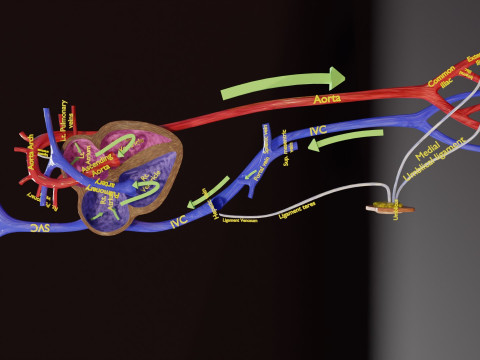

The model meshes include adult circulation versus circulation in Tetralogy of Fallot (TAF), arrow labels and text labels. The blood flow in a patient with Tetralogy of Fallot is outlined in this model. To contrast it to normal blood circulation a separate model of normal circulation is included. The Tetralogy of Fallot (OVER RIDING OF AORTA, PUL STENOSIS, VENTRICULAR SEPTAL DEFECT, RIGHT VENTRICULAR HYPERTROPHY), fossa, ligament teres , venosus, and arteriosus are duly depicted with proper labelling and blood flow directional arrows. Excellent model for teaching, demonstration and knowlegde of human body. The models include both procedural and image textures blend files separately. The texture file include diffuse, roughness and normal png and jpeg based on non overlapping UV maps.